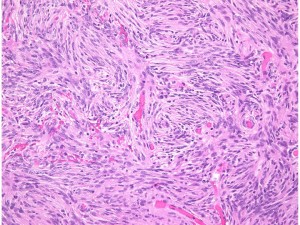

storiform pattern(長嶋和郎先生の病理教室)

紡錘形細胞が放射状に配列する所見でstoriform patten (花むしろ)、またはcartwheel (車輪)状に似た様子が見られます。軟部腫瘍であるfibrous histiocytomaで良く見られるものです。本例ではCP-angle meningiomaに見られた所見で、fibrous meningiomaの診断です。MIB-1 indexはやや高く8%でしたが、壊死や異型性は見られず、Grade 1相当とみなされます。HE x200